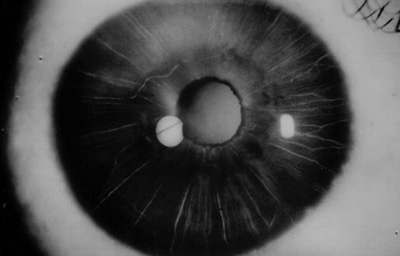

Paciente masculino de 18 años, estudiante a quien ( 10) dias antes , picadura de “avispa negra” en el Ojo Derecho en Sasaima, tratado con antibióticos y antiin amatorios corticoides, y Midriacyl 3 al día. Al examen: Edema corneal, Nubécula superior a las 12, PK ́s en Endotelio, Tono digital aumentado, Iris con atro as estromales, pupila en midriasis. AVsc. 0.33 , TO: 20 - Ojo Izquierdo sin alteraciones, (Foto No 3)

Foto 3 - Picadura en su estado inicial

Se inicia tratamíento con una inyección subconjuntival de Decadrón semanal (5 inyecciones) , Tobrex ( colirio) cada 2 horas, Pred F ( Prednisolona 1%)cada hora, Timolol 0.5 cada 12 horas y Atropina ( colirio) cada 8 horas; se hace Endoteliografía comparativa entre Ambos ojos. (Fotos No 4-5)

Foto 4 - Endotelio del OD afectado

El tratamiento es mantenido sin cambios durante el primer mes con controles periódicos cada 6 días. En el segundo mes, la córnea es trasparente con leucoma superior, Tono ocular digital blando; se reduce la medicación manteniendo el Pred F cada 2 horas, Timolol cada 12 horas y Tobrex 2 gotas al día.

Al tercer mes córnea trasparente con despigmentación del estroma iridiano, No hay transiluminación en el Iris. TO: 13 aplanático de Goldman, se inicia catarata subcapsular anterior.

A los 6 meses se realiza angiografía del Iris que muestra en las fases tardías la existencia de exudación en el estroma superior, pupila de 3.0mm normoreactiva (Foto No 6 y 7), y se formula Pred F nuevamente cada 2 horas durante 1 mes con reducción progresiva hasta el siguiente control.

A los 18 meses se realiza una segunda angiografía del Iris,(Foto No 8 ) mostrando ausencia de exudación; la córnea es trasparente con leucoma tenue superior, despigmentación del estroma iridiano en 360o con pupila de 3.0mm normoreactiva (Foto No 9), opacidad subcapsular anterior en el cristalino y Refracción: Plano ( -1.25 x 180a) 0.80. Se sugiere mantener Pred F 1 gota cada 5 días.

Foto 6 Angiografìa a los 6 meses con Exudación en el Iris

Foto 7 Foto del OD a los 6 meses

mostrando edema a las 12 y despigmentación del Iris en 360o

Foto 8 A los 18 meses, Angiografía sin exudación, solo despigmentacióno

Foto 9 Foto a los 18 meses post tratamiento

Ultimo control a los 28 meses del accidente, con ojo OD tranquilo TO: 10, córnea trasparente con leucoma superior residual, despigmentación del Iris en 300o con pupila normoreactiva y opacidad anterior en el cristalino. Agudeza Visual mejor corregida 0.80